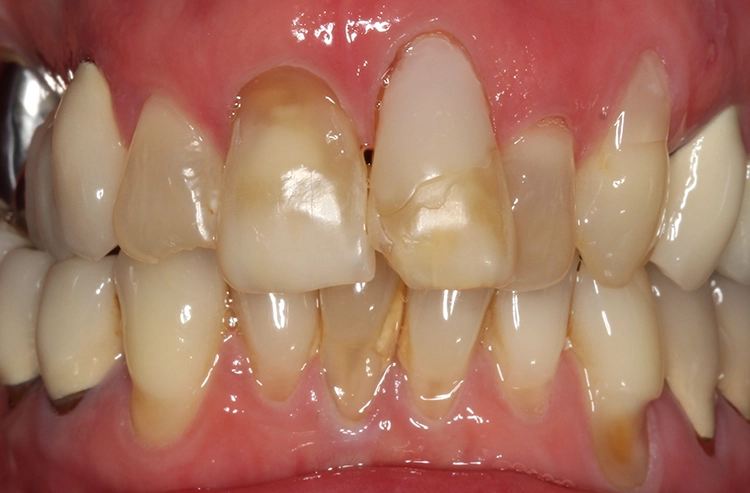

Bei der 61-jährigen Patientin imponierten unterschiedlichste Befunde, die ein ästhetisches Gesamterscheinungsbild gerade der Oberkieferschneidezähne deutlich beeinträchtigten (Ausgangsbefund Bild oben): Labiale und inzisale Zahnhartsubstanzdefekte unterschiedlichster Ausprägung an allen Inzisivi, Verfärbungen der Zähne, eine Fehlstellung sowie multiple Rezessionen und keilförmige Zahnhalsdefekte, die zum Teil von diversen Vorbehandlern mit Zahnhalsfüllungen versorgt worden waren. Es zeigte sich ein Gewebeüberschuss in regio 22, der zumindest teilweise durch die Elongation und Retrusion des Zahnes 22 bedingt zu sein schien. Diese Kombination führte zu einem disharmonischen Gingivaverlauf im Ober- und im Unterkiefer.

Der Wunsch der Patientin zur ästhetischen Neuversorgung bezog sich primär auf die Oberkieferfront. Dabei kam eine kieferorthopädische Therapie für sie nicht infrage. Fokus in der Beratung lag auf der mukogingivalen Grenzlinie: Vollkeramische Restaurationen können zwar auch bei Befunden wie dem vorliegenden eingesetzt werden, das ästhetische Gesamtbild ist dann jedoch ziemlich eingeschränkt, wenn eine derartige Asymmetrie der Gingivaverläufe der einzelnen Zähne besteht.

Die Patientin wurde eingehend über die Möglichkeiten und das operative Vorgehen der präprothetischen Mukogingivalchirurgie aufgeklärt: Die „Zahnfleischästhetik“ kann durch einen Rückgang, auch aber durch einen Überschuss von Gewebe negativ beeinflusst werden. Korrekturen von diesen Missverhältnissen können demnach durch unterschiedliche chirurgische Maßnahmen vorgenommen werden. Aufgrund von Statur und Gesichtsform der Patientin erschienen die Zähne 13 bis 11 nicht zu lang, weshalb gemeinsam mit der Patientin lediglich eine Korrektur des Gingivaverlaufes im 2. Quadranten eingeplant wurde.

So sollte an den Zähnen 21 und 23 eine Rezessionsdeckung mit Verdickung des Gewebes und an Zahn 22 eine chirurgische Kronenverlängerung durch Exzision der Gingiva ohne Osteotomie erfolgen (Low-Crest-Typ). Der Verlauf der Schneidekantenlängen und die Zahnstellung sollten in einem 2. Schritt durch Vollkeramikteilkronen bzw. Veneers mit Inzisalfassung harmonisiert werden. In der Behandlungsplanung dieses Falles kam erschwerend hinzu, dass 3 verschiedene parodontalchirurgische Behandlungsindikationen zusammenkamen: